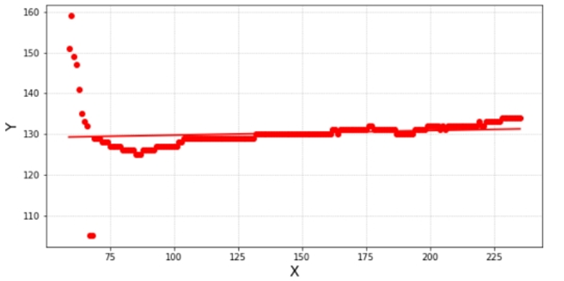

由于舌体大致呈现对称形态,故中轴线应将近垂直水平轴。为方便计算,将像素点标记图旋转90度,那么舌体中轴线应与水平轴的夹角为0,即tanα=0。将标记中轴线上的点进行直线拟合(y=kx+b),若舌体呈现垂直状则k应趋近于0,即k→0。经过不断测试不影响后续判断的k的取值范围应是-0.2~0.2。若用户上传的舌体图片拟合直线的斜率超出k的取值范围,则提示用户重新拍摄。直线拟合图如下:

经过不断测试不影响后续判断的k的取值范围应是-0.2~0.2!